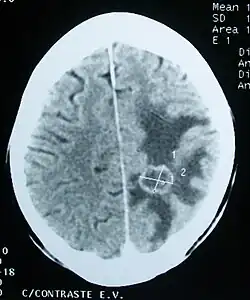

CT scan of a brain tumor, with its diameters marked as an X. There is hypoattenuating (dark) peritumoral edema in the surrounding white matter, with a "finger-like" spread.

Medical imaging plays a central role in the diagnosis of brain tumors. Early imaging methods – invasive and sometimes dangerous – such as pneumoencephalography and cerebral angiography have been replaced by non-invasive, high-resolution techniques, especially magnetic resonance imaging (MRI) and computed tomography (CT) scans.[42] MRI with contrast enhancement is the preferred imaging test in the diagnosis of brain tumors.[24][43] Glioblastomas usually enhance with contrast on T1 MRI weighted MRI imaging, and on T2 with FLAIR imaging showing hyperintense cerebral edema.[24] Low grade gliomas are usually hypointense on T1 MRI, and hyperintense with T2 with FLAIR MRI. Meningiomas are usually homogenously enhanced with dural thickening on MRI.[24]